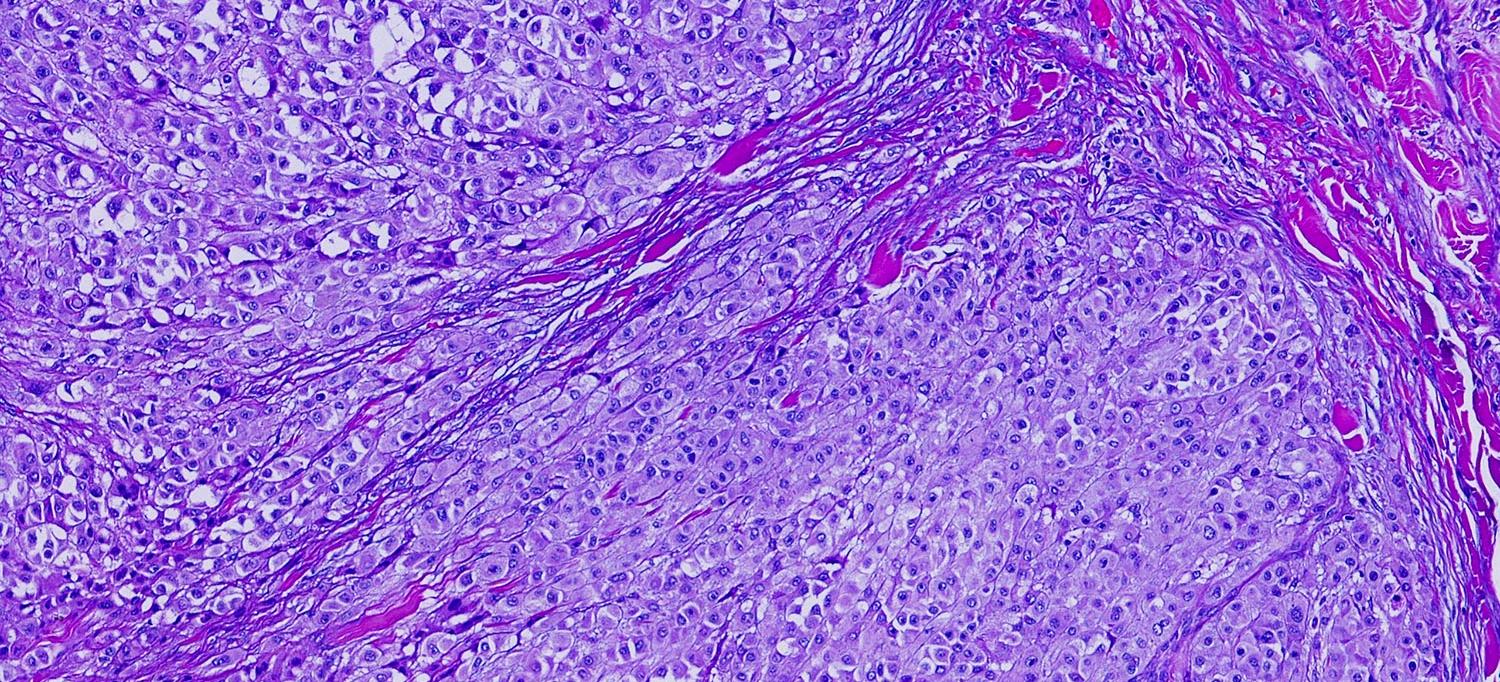

For the investigation, the researchers collected 302 images of tumor tissue samples from 121 men and women treated for metastatic melanoma with immune checkpoint inhibitors at NYU Langone’s hospitals. Then, they divided these slides into 1.2 million portions of pixels, the small bits of data that make up digital images. These were fed into the computer along with factors such as the severity of the disease, which kind of immunotherapy regimen was used, and whether a patient responded to the treatment.